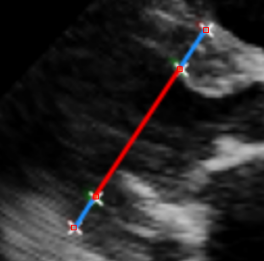

Left Ventricular Hypertrophy (LVH), one of the leading predictors of adverse cardiovascular outcomes, is the condition where heart’s mass abnormally increases secondary to anatomical changes in the Left Ventricle (LV) [10]. These anatomical changes include an increase in the septal and LV wall thickness, and the enlargement of the LV chamber. More specifically, Inter-Ventricular Septal (IVS), LV Posterior Wall (LVPW) and LV Internal Diameter (LVID) are assessed to investigate LVH and the risk of heart failure [21]. As shown in Figure 1 (a), four landmarks on a parasternal long axis (PLAX) echo frame can characterize IVS, LVPW and LVID, and allow cardiac function assessment. To automate this, machine learning-based (ML) landmark detection methods have gained traction.

It is difficult for such ML models to achieve high accuracy due to the sparsity of positive training signals (four or six) pertaining to the correct pixel locations. In an attempt to address this, previous works use 2D Gaussian distributions to smooth the ground truth landmarks of the LV [9, 13, 18]. However, as shown in Figure 1 (b), for LV landmark detection where landmarks are located at the wall boundaries (as illustrated by the dashed line), we argue that an isotropic Gaussian label smoothing approach confuses the model by being agnostic to the structural information of the echo frame and penalizing the model similarly whether the predictions are perpendicular or along the LV walls.